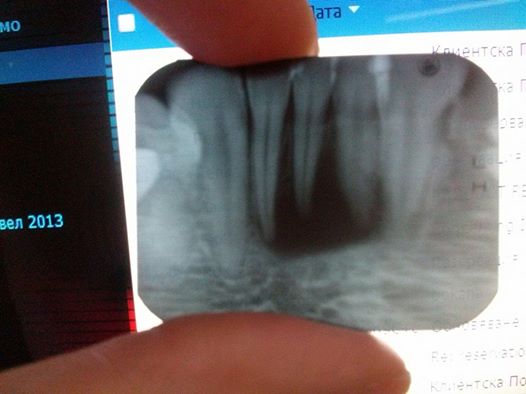

Здравейте Д-р Камбов, Прикачила съм снимка на предните си три долни зъби. Има образование което не могат в моя град да преценят какво е точно. Всеки зъболекър ми казва различно и ми предлага различни решения. Попринцип тези зъби не ме болят, но ми излиза гнойна торба на венеца, пия антибиотик и минава, но след три четири седмици се появява отново и става по-зле и по-зле. Много ще Ви благодарна ако ми отделите 5 минути и кажете и своето мнение. Поздрави!

10262242_10201924265128008_1769237211353980783_n.jpg

10262242_10201924265128008_1769237211353980783_n.jpg (25.05 KiB) Прегледано 736 пъти